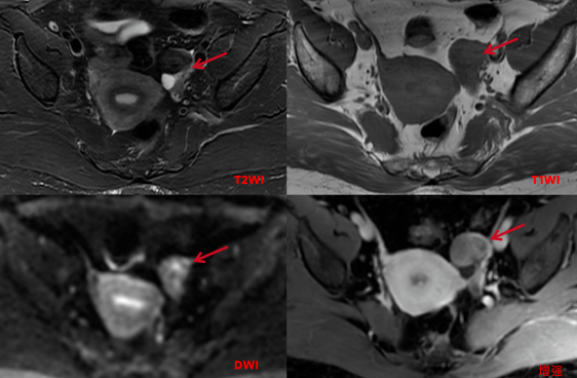

盆腔MRI平扫及增强:左侧附件区可见稍长T1短及稍短T2信号,大小约25x30x30mm,T2WI压脂像呈稍低信号,边界清楚,边缘较光滑,DWI呈周边不均匀稍高信号,中心信号稍低, 增强扫描不均匀中等强化,其后方另见多个小囊状长T2信号,增强扫描病变囊壁稍厚,光滑,轻微强化。

影像诊断:左侧附件区囊实性占位,倾向良性可能性大,Brenner瘤或卵泡膜纤维瘤可能性大,建议临床活检。

鉴别诊断:子宫阔韧带肌瘤并钙化、颗粒细胞瘤